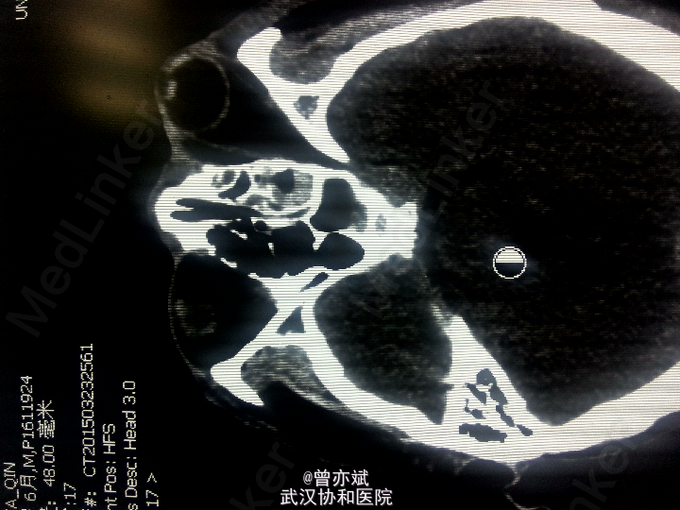

查体:T 36.9℃,P 70次/分,R 20次/分,BP 128/82mmHg,查体不合作,神志浅昏迷,营养发育良好,皮肤及淋巴结未及明显异常,头颅大小正常,无畸形,头发分布正常,左额部软组织损伤,心肺腹未及明显异常。双下肢无水肿,生理反射存在,病理反射未引出。 专科查体:神志浅昏迷,GCS评分3+3+4分,左侧瞳孔直径6mm,对光反射消失,右侧瞳孔直径4mm,对光反射存在,四肢肌力2级,生理反射存在,病例反射未引出。 辅助检查:外院及我院急诊CT示左侧额部硬膜外血肿。急诊CT:1、左侧额部硬膜外血肿,厚度为23mm;2、少量蛛网膜下腔出血;左侧额骨线性骨折累及左侧眶顶、内侧壁及眶突,左侧眼眶内侧壁局部凹陷,考虑为外上性改变,左侧筛窦积液、积血、蝶窦积液。